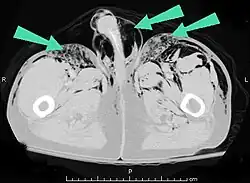

Additionally, it may result from self-injection of air during illicit drug use, particularly in individuals who inject substances intravenously or into unusual sites. There have been documented cases of subcutaneous emphysema occurring in various body regions, including the scrotum, secondary to such self-induced air injection during substance abuse.[23]

Air can be trapped under the skin in necrotizing infections such as gangrene, occurring as a late sign in gas gangrene,[2] of which it is the hallmark sign. Subcutaneous emphysema is also considered a hallmark of Fournier gangrene.[27] Symptoms of subcutaneous emphysema can result when infectious organisms produce gas by fermentation. When emphysema occurs due to infection, signs that the infection is systemic (i.e. that it has spread beyond the initial location) are also present.[9][21]

Subcutaneous emphysema is usually benign.[1] Most of the time, SCE itself does not need treatment (though the conditions from which it results may); however, if the amount of air is large, it can interfere with breathing and be uncomfortable.[29] It occasionally progresses to a state "Massive Subcutaneous Emphysema" which is quite uncomfortable and requires surgical drainage. When the amount of air pushed out of the airways or lung becomes massive, usually due to positive pressure ventilation, the eyelids may swell so much that the patient cannot see. The pressure of the air may impede the blood flow to the areolae of the breast and skin of the scrotum or labia which can lead to necrosis. The latter are urgent situations requiring rapid, adequate decompression.[30][31][32] Severe cases can compress the trachea and do require treatment.[33]